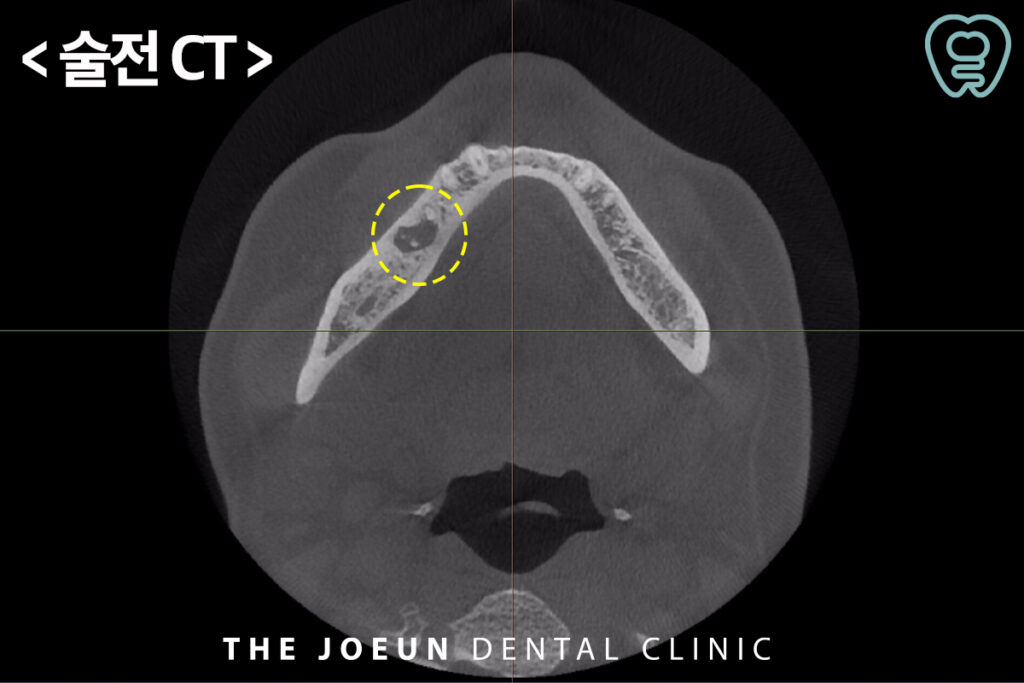

오늘은 오래 된 치아 뿌리의 염증으로 인해 자연치를 발치하고 뼈이식 후 6개월 만에 임플란트를 식립하여 완성하신 환자분을 소개해 드리도록 하겠습니다. 환자분께서는 오랜만에 구강 검진 차 내원하셨다가 우연히 왼쪽 아래 어금니의 커다란 염증을 알게 되셨는데요. CT 상에서도 확연하게 뿌리 주위를 감싸고 있는 까만 염증 부분을 확인할 수 있었습니다. 평상시 불편을 느낄만한 큰 통증이 없었기 때문에 전혀 모르고 계셨지만 이미 잇몸뼈를 많이 녹인 상태로 발치를 하더라도 바로 임플란트 진행이 불가능할 것이라고 판단되어 뼈이식 후 충분한 기간을 기다려준 뒤 임플란트 식립을 진행하기로 하였습니다.

먼저 염증이 심한 치아를 발치하고 뼈이식을 진행하였습니다.